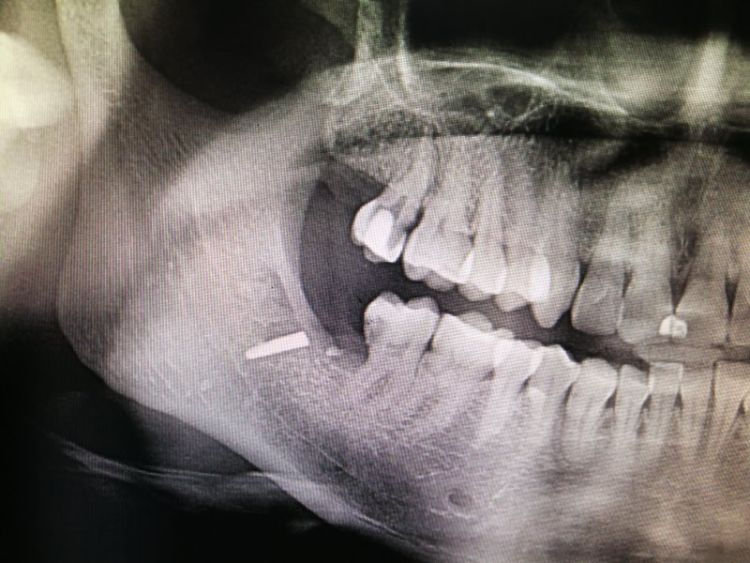

牙窝内的金属物。李女士家住宝安松岗,20多天前,因为智齿疼痛,去了附近一家小诊所拔智齿。“当时好像是挺难拔的,搞了三个多小时。”李女士说。而手术期间,她也打了麻药,并不知道当时具体发生了什么。现在回忆起来,隐约想起医生在手术过程中,好像说了一句“哎呀......断了......”之类的话。李女士表示,自己术后感觉到右侧脸部有一些硌舌头的感觉,但因为刚拔完智齿,以为是正常反应,于是简单询问了一些关注事项之后,便回家了。医生也没有提起任何有关于手术中间有什么异常的事情。但之后,李女士牙龈开始出现发炎和肿痛,一开始她依然以为是拔智齿后的正常反应,没想到之后越来越严重。手术部位逐渐发脓,脸部也火辣辣的疼,20多天都未能缓解。之后不得不前往医院做进一步检查治疗。

李女士口腔内的金属物。这一检查,把她吓了一跳。据其在松岗人民医院口腔科拍摄的x光片显示:她之前拔掉的智齿牙窝里,残留了两节金属物,并且已经没入很深,快要接近下颌神经管了。如果再深一点,可能会导致其面部神经损坏。“我听到,差点吓哭了。”李女士说。自己当时因为想省点钱,就去了小诊所,没想到竟然发生了这样的事情。好在后来去医院还算及时,医护人员确定位置和异物大小等情况后,利用超声骨刀把李女士牙窝中的异物取了出来。后经十余天的输液治疗,李女士的情况已经基本恢复。

取出的金属物长约1公分。那么,嵌入李女士牙窝中的金属物质到底是什么呢?松岗人民医院口腔科医生石健介绍,医院接诊后,为患者拍摄了X光片。从X光片可以看到,李女士拔牙创口有一个密度很高的金属影,长度约1公分。经联系李女士拔牙的诊所医生了解到,这个异物可能是拔牙用具“压挺”的尖端碎片。“牙挺是靠撬力来拔出牙齿的,医生如果用力不当,有时会将牙挺尖端折断,遗留在患者的牙窝内。”石健医生说。据介绍,因异物嵌入很深,快要接近神经管,取出时风险较大。后经商议,决定使用超声骨刀帮患者将异物取出。李女士表介绍,事发后,当时为其拔牙的小诊所对此进行了道歉和赔偿。